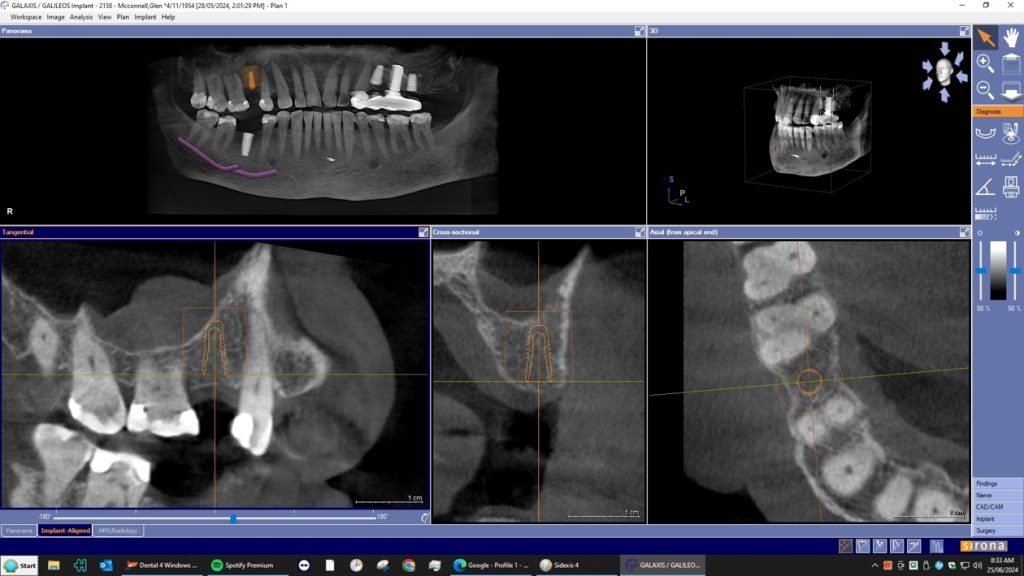

A dental Implant is a titanium “root” that integrates directly with the surrounding bone and replaces the function of the natural tooth. Neoss Implants are made using the best quality medical grade titanium, which is well known for its proven biocompatibility, and have a treated surface to facilitate bone integration.

Your dentist will inform you which implant treatment is most suitable for you.